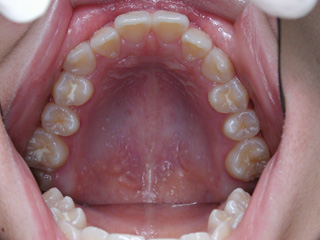

診断名:下顎左右第二小臼歯先天欠如、下顎左方偏位を伴う下顎前突

使用した主な装置名:マルチブラケット装置、オーソアンカー SMAPシステム

抜歯/非抜歯および抜歯部位:抜歯(下顎左右第二乳臼歯)

下顎の第二小臼歯の先天欠如が見られました。先天性欠如歯がある場合、上下顎小臼歯抜歯のスタイルで歯数を合わせる事も多いのですが、抜歯数が増えるのが難点です。 プロファイル、下顎前突、非対称の問題を考慮して下顎にオーソアンカー SMAPシステム を植立し、下顎晩期残存の乳歯のみを抜歯し、永久歯の抜歯は行わず空隙を閉鎖致しました。大臼歯の咬合についてはIII 級仕上げ という噛み合わせにしています。